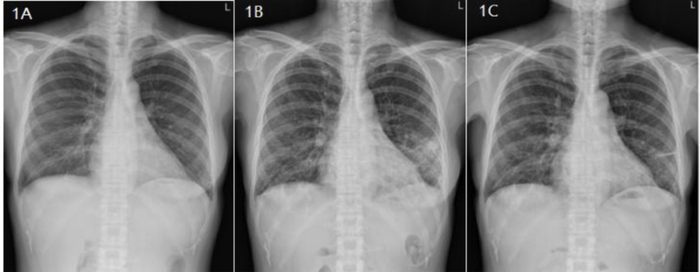

胸部CT示:小叶间隔增厚、多发小叶中心结节和散在薄壁囊肿,尤其以双侧中下肺野为著(图2A-D)。

图2A-D、E-H 2015年12月和2016年7月患者胸部CT影像对比

后续随访情况:患者定期检查肺功能,起初提示肺活量参数较前均都有所改善,随后呈现相对稳定的趋势(表2)。7个月后随访胸部CT示,网状和囊性病变没有明显进展(图2E-H)。